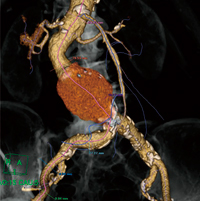

一方,大動脈では解析軸の自動抽出が従来のソフトウェアではうまくいかないことがしばしば経験されていた。今回の大血管用の血管解析ソフトウェアでは,大動脈軸の自動抽出能が向上しただけでなく,大動脈分枝を含めたツリー状の抽出も可能となっている(図1)。これにより検討の対象となりうる血管の中心線を速やかに,かつ網羅的に抽出することができ,効率的な解析が可能になる。

図1 血管抽出後の3D VR画像

アクティブな解析軸(桃色線)に加え,網羅的に抽出されたその他の解析軸(青線)がツリー状に表示されている。